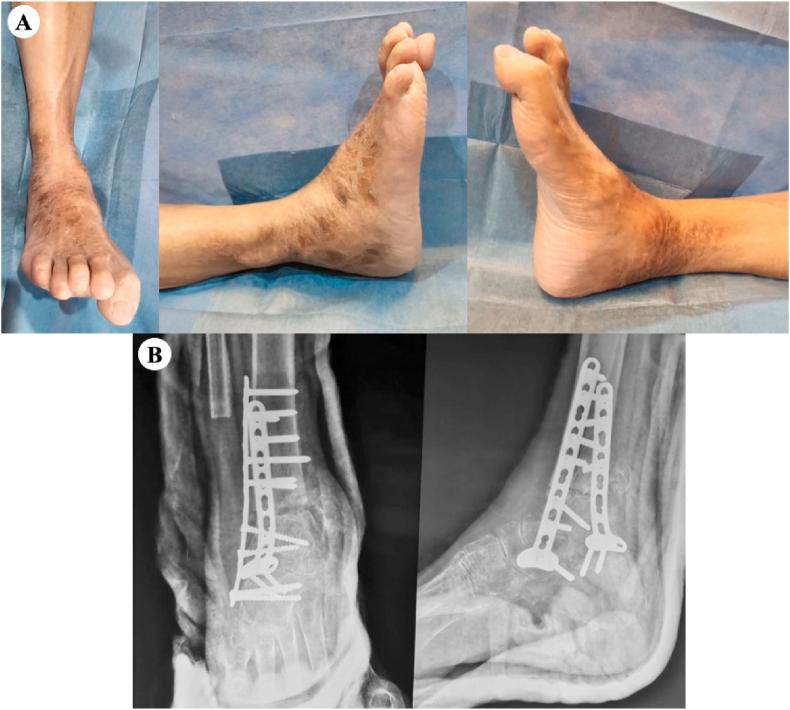

Ankle arthrodesis is one of the managements for a significantly unstable Charcot ankle. Some of the methods of internal fixation for ankle arthrodesis include the use of intramedullary nails, screws, and plates. Ankle arthrodesis using intramedullary nails has become more popular. However, studies evaluating the use of plate fixation, particularly double posterior lateral plating, are limited. We report the clinical and radiological outcomes of double posterior lateral plating ankle arthrodesis in three diabetic Charcot ankle patients.

Three patients, aged 73, 67, and 65 years old, complained of ankle pain and with a history of type 2 diabetes mellitus. The physical examination revealed swelling and erythema without a sign of active infection. The radiological examination showed ankle deformity, and the American Orthopaedic Foot & Ankle Society (AOFAS) Ankle-Hindfoot scores were 5, 10, and 0, respectively. All patients were diagnosed with a diabetic Charcot ankle and underwent ankle arthrodesis using double posterior lateral plating. Four months and six months follow up revealed talus union, improved ankle deformity, and improved AOFAS Ankle-Hindfoot scores to 70, 76, and 73, respectively.

Various methods of ankle arthrodesis are retrograde intramedullary nails, screws, and plates. In this report, we opt for plate fixation because it allows for stable internal fixation, adequate compression, high angular stability, and a lower irreversible deformation in osteoporotic bone.

踝关节融合术是治疗严重不稳定型夏科氏踝关节的方法之一。踝关节融合术的一些内固定方法包括使用髓内钉、螺钉和钢板。使用髓内钉进行踝关节融合术越来越受欢迎。然而,评估钢板固定,特别是双后外侧钢板固定的研究有限。我们报告了三例糖尿病性夏科氏踝关节患者采用双后外侧钢板固定踝关节融合术的临床和放射学结果。

三名患者,年龄分别为73岁、67岁和65岁,主诉踝关节疼痛,有2型糖尿病病史。体格检查发现肿胀和红斑,无活动性感染迹象。放射学检查显示踝关节畸形,美国矫形足踝协会(AOFAS)踝-后足评分分别为5分、10分和0分。所有患者均被诊断为糖尿病性夏科氏踝关节,并接受了双后外侧钢板固定的踝关节融合术。随访4个月和6个月时,距骨愈合,踝关节畸形改善,AOFAS踝-后足评分分别提高到70分、76分和73分。

踝关节融合术的各种方法包括逆行髓内钉、螺钉和钢板。在本报告中,我们选择钢板固定,因为它能提供稳定的内固定、足够的加压、高角度稳定性,并且在骨质疏松性骨中产生较低的不可逆变形。